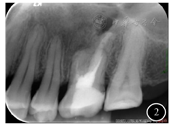

面照;B:26颊面照影像学检查:根尖片示26根尖区椭圆形低密度影(图2)。锥形束CT(cone beam computed tomography,CBCT)示26根尖区至左侧上颌窦底壁见不规则骨质缺损,缺损边缘可见硬化。缺损区偏远中腭侧见一类椭圆形低密度影,边缘硬化,范围约13 mm×10 mm×8mm,与骨缺损区相通。26见4根管,MB(近颊根管)、DB(远颊根管)、P(腭根管)根管内见充填物影,MB2(近颊根第二根管)内未见明显根管充填物影,根管钙化(图3)。

诊断:26根尖囊肿。诊断依据:1.病史:曾因26根尖囊肿行囊肿刮除术;2.病理学检查:囊肿刮除术标本镜下表现符合根尖囊肿;3.影像学检查:根尖片和CBCT示26根尖区存在边界清楚的低密度影。诊断明确,无需鉴别。

根尖片示26根尖区椭圆形低密度影。CBCT示26根尖区至左侧上颌窦底壁见不规则骨质缺损,缺损边缘见硬化,缺损区偏远中腭侧见一类椭圆形低密度影,边缘硬化,范围约13 mm×10 mm×8 mm,与骨缺损区相通;26见4根管,MB2内未见明显根管充填物影,根管钙化。诊断:26根尖囊肿。